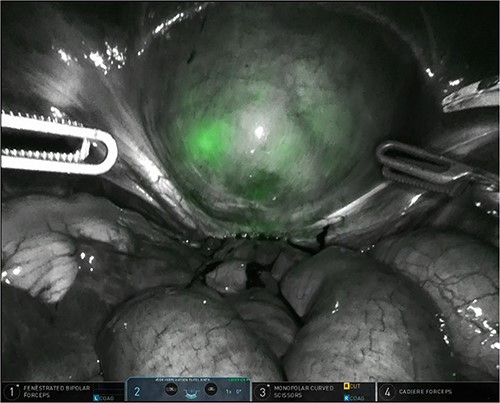

The patient was planned for a robotic resection of the endometriosis nodule and hysterectomy by an experienced robotic gynecological surgeon. The patient was placed on a PinkPad (Kebomed Europe AG) in a lithotomy position. Cystoscopy was performed with placement of ureteral stents. Double-J stents were guided up to the kidneys. Instillation of 200 ml physiologic water with 2 cc of ICG (1.9 mg/cc) in an empty bladder, with subsequent clamping of the urinary catheter (Fig. 3). The da Vinci Xi robot platform (Intuitive Surgical Inc.) was used. Instruments used were: bipolar fenestrated forceps, unipolar scissor, Cadière forceps, and Vessel Sealer Extend. Circumferential incision, dissection and detachment of the endometriotic nodule from the posterior bladder wall was performed under guidance of NIR imaging and ICG, whilst the endometriosis nodule remained stuck on the uterine isthmus (Fig. 4; Supplementary Video). During the dissection, perforation of the bladder mucosa could be avoided, with transparency of the bladder mucosa by ICG. During the hysterectomy part, the bladder catheter was unclamped. The posterior bladder wall was repaired longitudinally. The muscular layers and serosa of the bladder were sutured with Monocryl 3/0 in a two-layer closure (Fig. 5). The bladder was filled with 200 cc of physiologic water with ICG, no bladder leakage nor clear transparency by ICG of the posterior bladder wall was seen. The total operative time was 120 min. The total blood loss was 25 mL. There were no perioperative complications. The length of the hospitalization was 48 hrs. Oxybutynin was given to prevent bladder spasms from the urinary catheter and/or stents. The Foley catheter was removed after 9 days, and the ureteral stents removed after 10 days. At the 2-week outpatient visit the patient was satisfied, and didn’t experience any pain nor urinary voiding problems.

Robotic dissection of the endometriosis nodule between the isthmus of the uterus and bladder; lateral dissection with bilateral transparency of ICG of the thin posterior bladder wall.